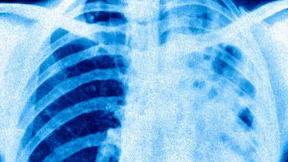

Tuberkulose galt bei uns lange als besiegte Krankheit, nun schlagen Experten Alarm: Die Erkrankung tritt wieder häufiger auf. Besondere Risikofaktoren sind Armut und Obdachlosigkeit.